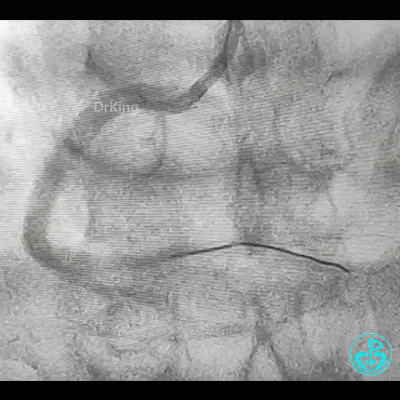

处理右冠,XB RCA,Sion、Sion blue导丝,2.0×20mm球囊。支架植入过程相当顺利,很快就完成,窃喜!心想后扩后马上结束!

植入3.5×29mm和3.5×24mm支架。